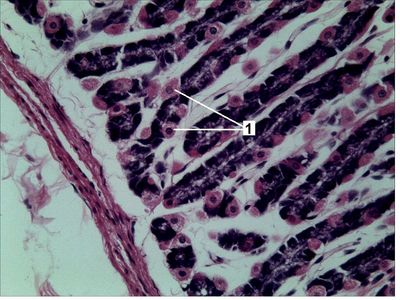

Question 13

Question

La imagen corresponde a una muestra histológica de estómago, las células indicadas con el número 1 corresponde a:

Answer

• Células principales o zimógenas

• Células parietales u oxínticas

• Células de Paneth

• Célula mucosa de superficie